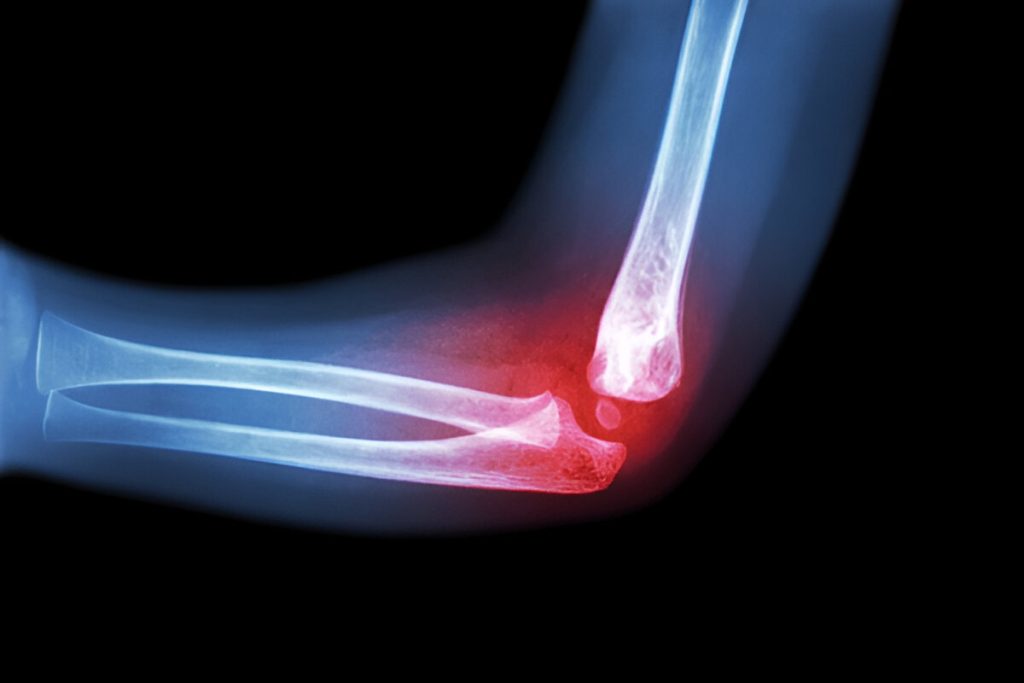

The lateral collateral ligament (LCL) of the elbow — also called the radial collateral ligament — is a key stabilizing structure on the outer (lateral) side of the elbow joint. It connects the lateral humerus (upper arm bone) to the radius (forearm bone) and helps resist varus stress, which pushes the forearm toward the body. The LCL also works with surrounding structures to maintain elbow stability during motion and protect against dislocation.

• MRI to confirm ligament damage

• X-rays to evaluate for bone or joint abnormalities